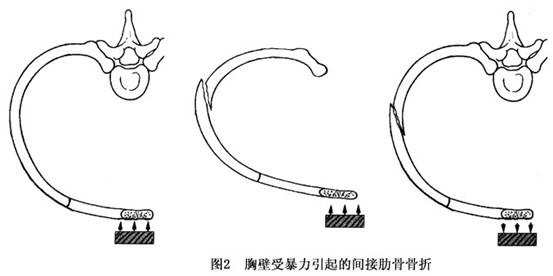

多根肋骨骨折 多根肋骨骨折的治療 多根肋骨骨折的原因 多根肋骨骨折怎麼辦 症状百科